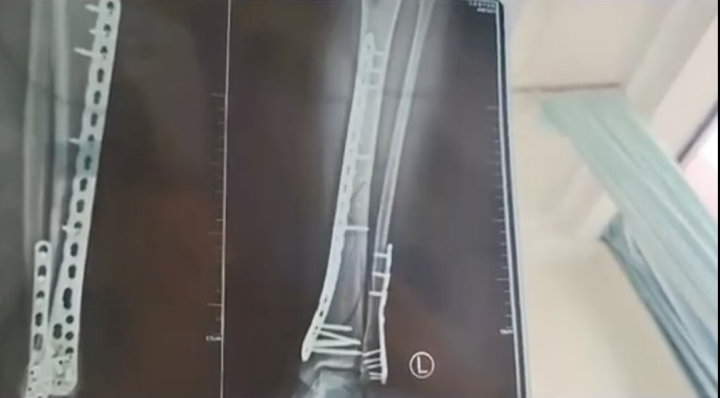

据悉,近日,甘肃兰州一位武女士称,母亲节当天,她穿7cm厚洞洞鞋下楼不慎崴脚摔倒,致使自己左腿粉碎性骨折……

武女士称,因为洞洞鞋的鞋底比较厚,脚掌中间又是凹进去的,自己下楼梯的时候正好踩到凹进去的地方,当时脚没有踩稳,整个人的重心往前扑,所有重力都集中在腿上,结果就骨折了。

武女士说,自己目前已做完手术在家休养,她也提醒大家,穿增高鞋要注意。